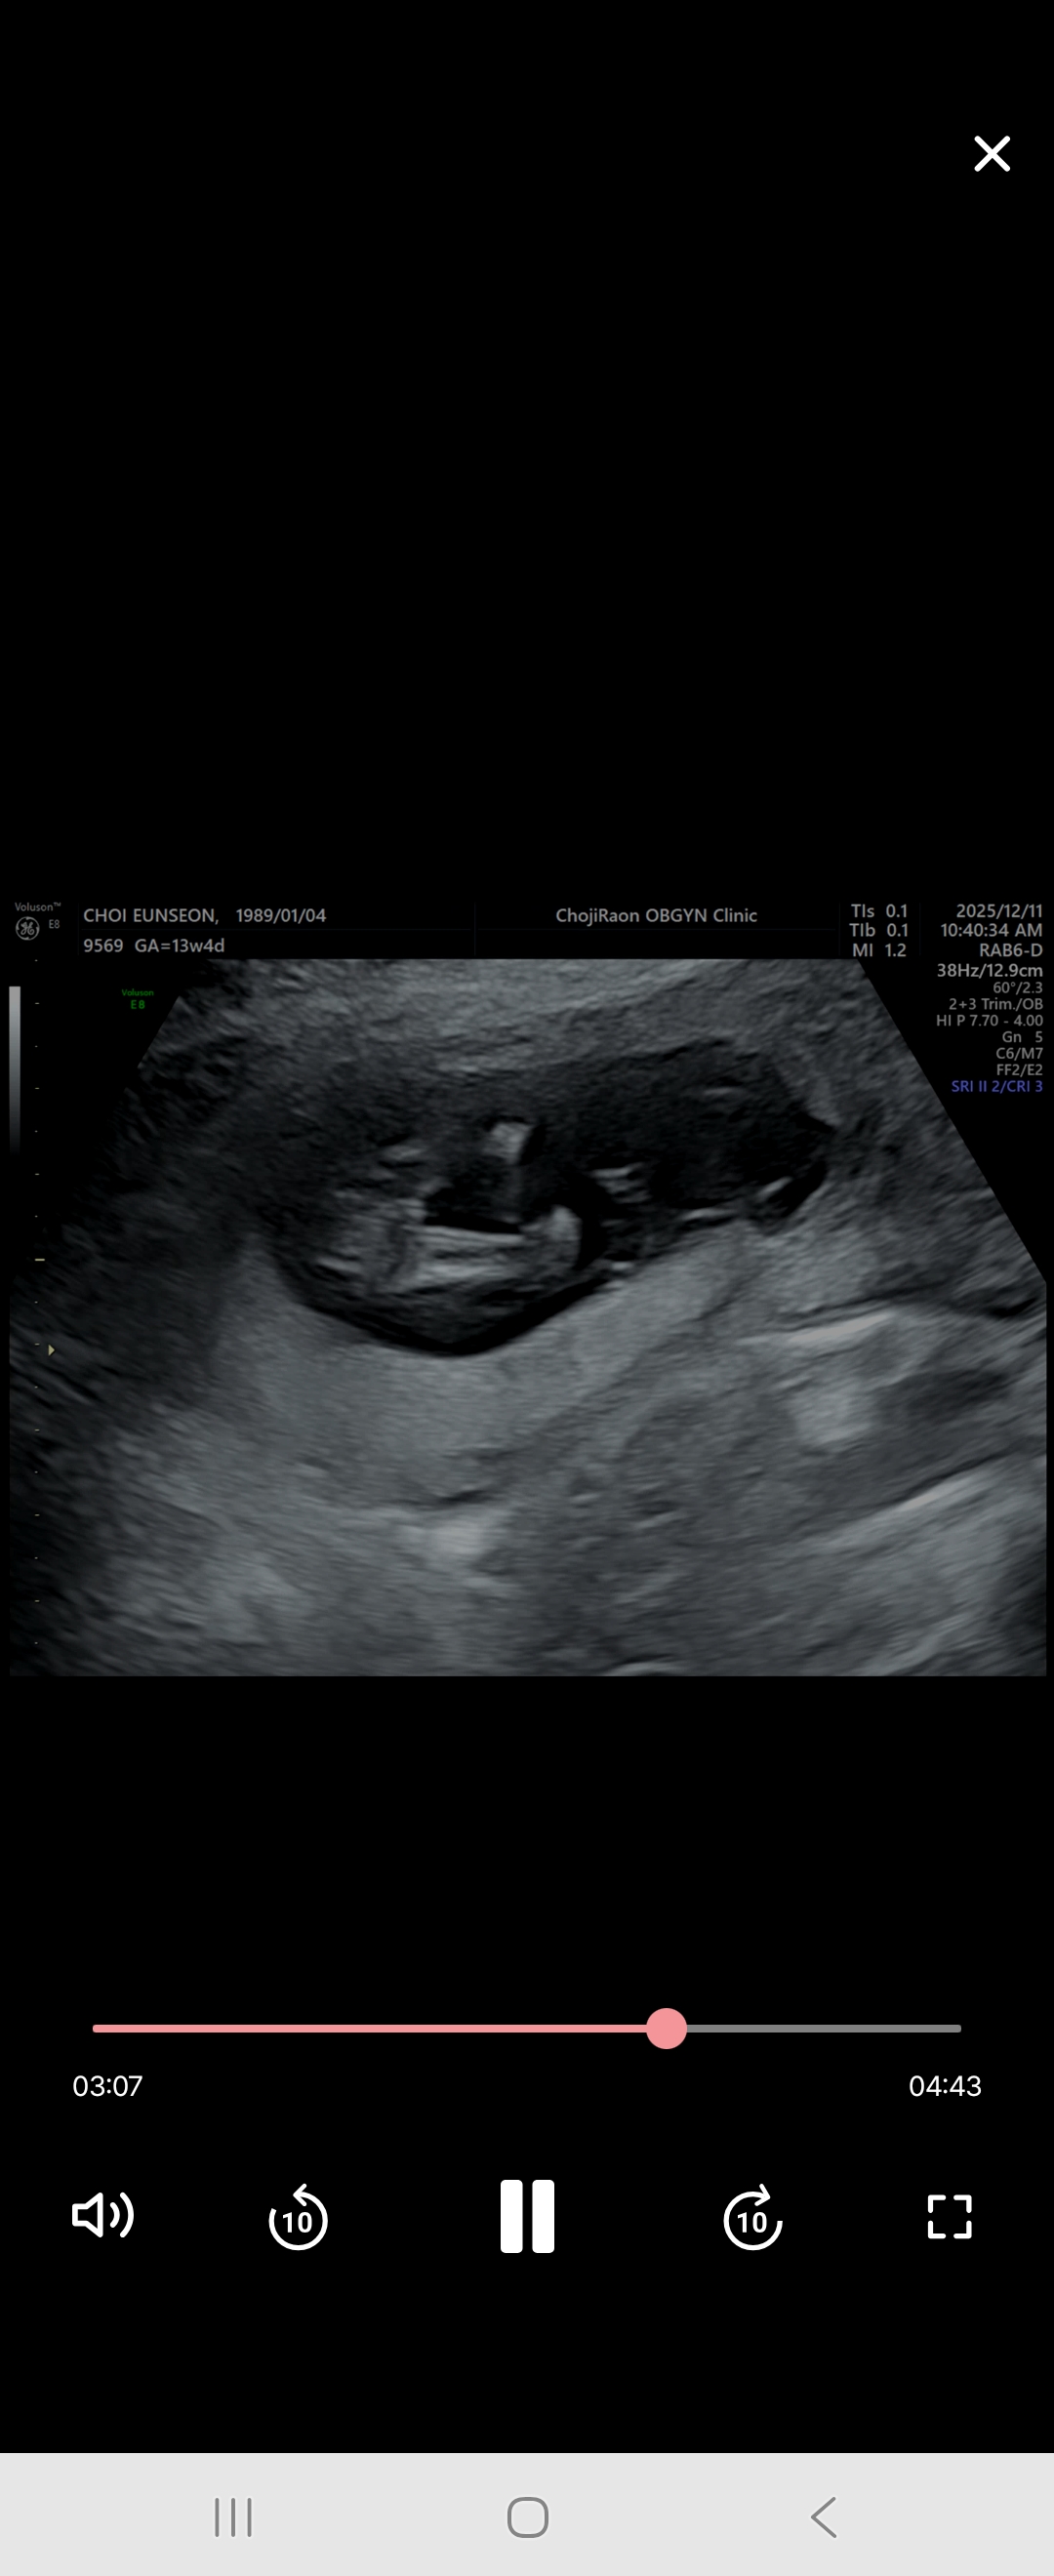

성별 참견좀 해주세용ㅎㅎ

다리 사이 사진인데 어때보이세용?!ㅎㅎ